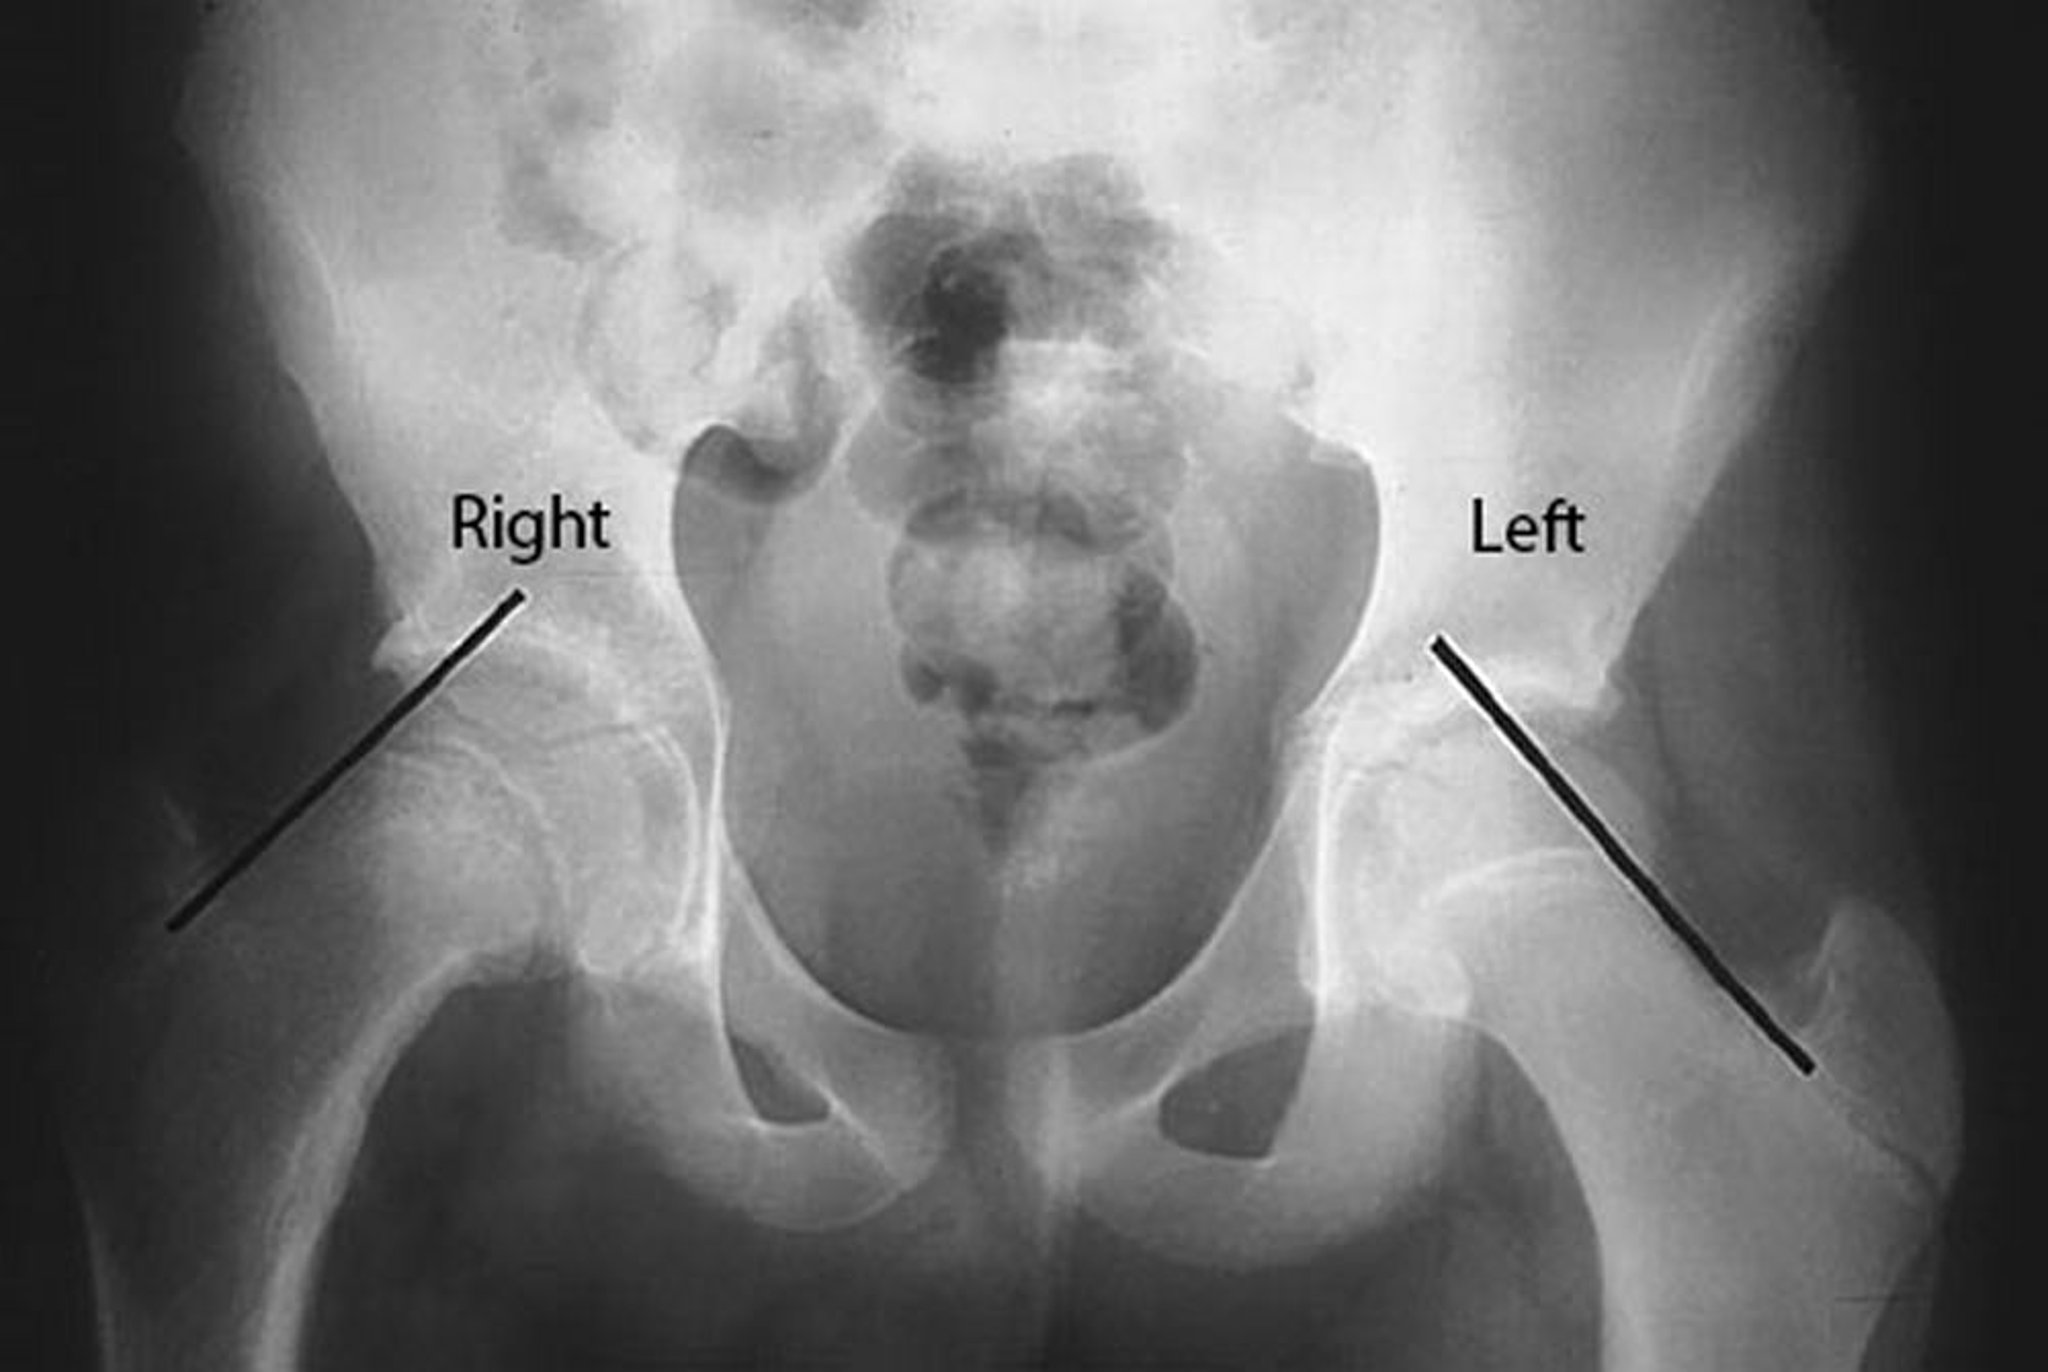

Épiphysiolyse de la tête fémorale

Des lignes de Klein sont tracées sur le bord supérieur du col fémoral chezce patient présentant une épiphysiolyse de la tête fémorale droite. Remarquer que la tête fémorale se trouve en dessous de la ligne de Klein du côté droit affecté, alors qu'une partie importante de la tête fémorale est au-dessus de la ligne de Klein du côté non affecté.